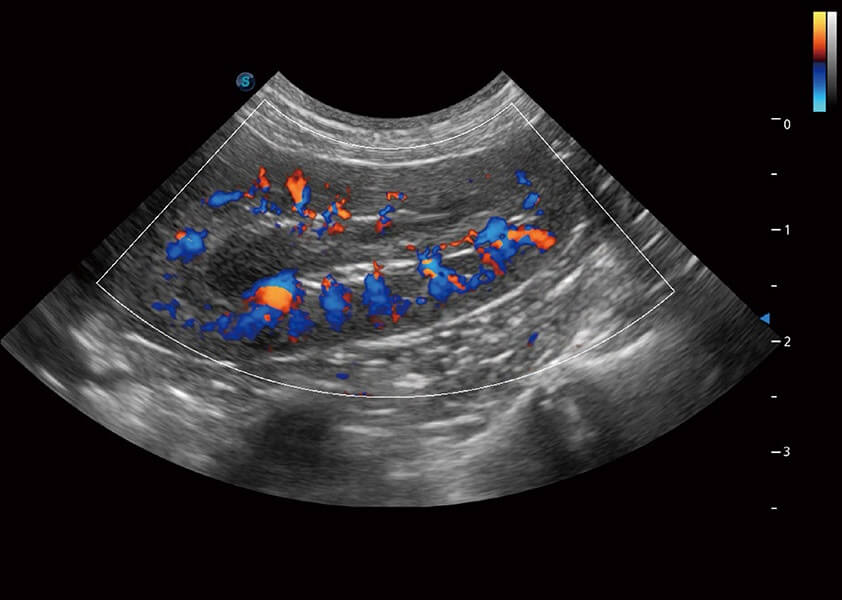

ProPet 60 作为一款高端台式动物超声设备,为动物医生的日常诊断提供了一系列贴合动物临床需求、解决临床实际问题的高级成像功能。凭借全系列高清探头,满足医生对腹部、心脏、生殖、浅表、肌骨等成像的所有需求,切实帮助您提升检查效率,提高诊断信心。

动物是人类最亲密的朋友和最值得信赖的伙伴。db真人体育官网也一直致力于探索动物专用的超声影像解决方案。 全新推出的ProPet系列,是db真人体育官网在动物超声影像智能化、专业化、精准化的一次跨越式革新。动物不能用言语来表述自己的不适,通过超声影像,ProPet系列搭建了动物医生与不同物种沟通的“桥梁”,为动物医生注入了“治愈之力”。